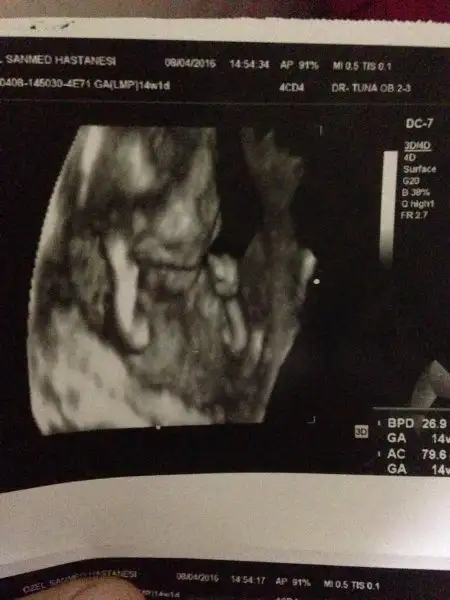

Öyle canım çok merak ediyorum zaten paşami :) zaten hiç yüzünü gostermedi kerata :)

Ay bende ya hep rüyamda mavi gözlü görüyorm görmcem ve eşimn amcaları mavi gözlü. Kv,eşim, annem ve bir görümcemde yeşil gözlü inşallh sağlıklı ve renkli gözlü olur:) kızımn kahverengi gözü bana çekmiş bari oğluşum renkli olsn inşallh ya tabi önce sağlıklı olsunda. Bizim keretada dört aylıkken yüzünü gösterdi çenesi eşim ve kızım gibi sivri benmde çook hoşuma gitti ya çok yakışıklı olacak ama inanıyorm ben bir kıvanç tatlıtuğ doğuracam gibi hissediyorm:))

Ablalar bakın 4 aylıkkenki foroğrafımız sizcede çok yakışıklı değilmiyiz:KK70:

masalah oglusuna :KK200::nazar::nazar::nazar: yeni bir jön mü dogacak diyosun:KK70::KK71: